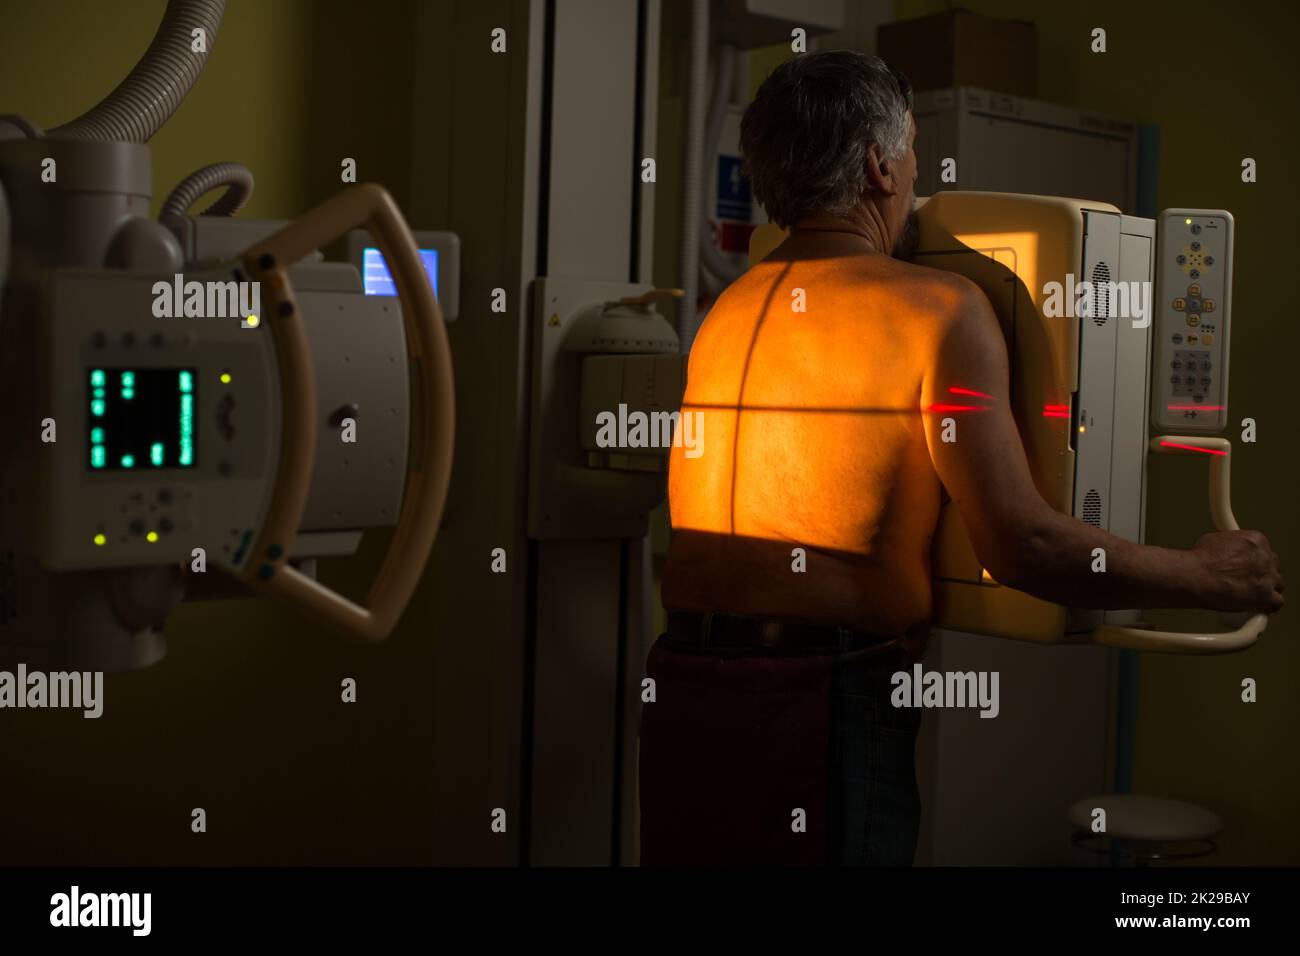

Senior man x-ray medical scan examination in a modern hospital (color toned image) Stock Photohttps://www.alamy.com/image-license-details/?v=1https://www.alamy.com/senior-man-x-ray-medical-scan-examination-in-a-modern-hospital-color-toned-image-image483326106.html

Senior man x-ray medical scan examination in a modern hospital (color toned image) Stock Photohttps://www.alamy.com/image-license-details/?v=1https://www.alamy.com/senior-man-x-ray-medical-scan-examination-in-a-modern-hospital-color-toned-image-image483326106.htmlRF2K29BAJ–Senior man x-ray medical scan examination in a modern hospital (color toned image)

Senior man x-ray medical scan examination in a modern hospital (color toned image) Stock Photohttps://www.alamy.com/image-license-details/?v=1https://www.alamy.com/senior-man-x-ray-medical-scan-examination-in-a-modern-hospital-color-toned-image-image483326111.html

Senior man x-ray medical scan examination in a modern hospital (color toned image) Stock Photohttps://www.alamy.com/image-license-details/?v=1https://www.alamy.com/senior-man-x-ray-medical-scan-examination-in-a-modern-hospital-color-toned-image-image483326111.htmlRF2K29BAR–Senior man x-ray medical scan examination in a modern hospital (color toned image)

Senior man x-ray medical scan examination in a modern hospital (color toned image) Stock Photohttps://www.alamy.com/image-license-details/?v=1https://www.alamy.com/senior-man-x-ray-medical-scan-examination-in-a-modern-hospital-color-toned-image-image483326115.html

Senior man x-ray medical scan examination in a modern hospital (color toned image) Stock Photohttps://www.alamy.com/image-license-details/?v=1https://www.alamy.com/senior-man-x-ray-medical-scan-examination-in-a-modern-hospital-color-toned-image-image483326115.htmlRF2K29BAY–Senior man x-ray medical scan examination in a modern hospital (color toned image)

Senior man x-ray medical scan examination in a modern hospital (color toned image) Stock Photohttps://www.alamy.com/image-license-details/?v=1https://www.alamy.com/senior-man-x-ray-medical-scan-examination-in-a-modern-hospital-color-toned-image-image483326119.html

Senior man x-ray medical scan examination in a modern hospital (color toned image) Stock Photohttps://www.alamy.com/image-license-details/?v=1https://www.alamy.com/senior-man-x-ray-medical-scan-examination-in-a-modern-hospital-color-toned-image-image483326119.htmlRF2K29BB3–Senior man x-ray medical scan examination in a modern hospital (color toned image)